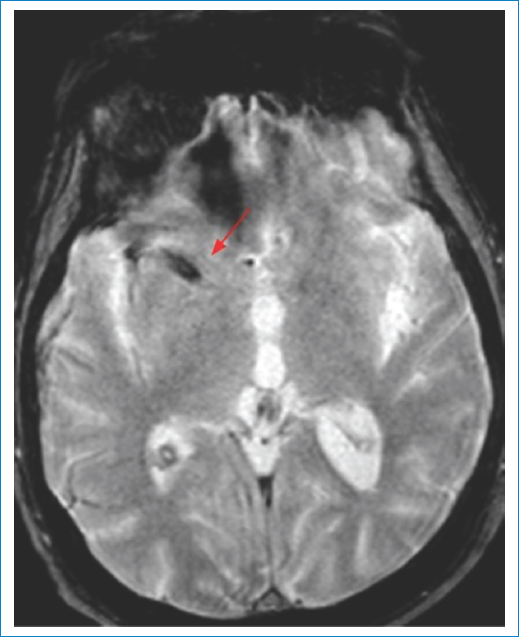

En la fase aguda, tanto la TC como la RM usando secuencias de susceptibilidad magnética nos permitirán la detección de hemorragias; aunque la RM es más sensible para la detección de hemorragias petequiales (microhemorragias), de hematomas o microsangrados previos, y en la detección de trombo intraluminal en vaso de mediano calibre. Puede observarse en la RM el equivalente al signo de la cuerda hiperdensa en las secuencias de susceptibilidad, signo que tiene una alta especificidad para detectar el sitio de la oclusión. La visualización del trombo en esta secuencia se relaciona con la presencia de un trombo rojo (desoxihemoglobina), asociada por lo general a etiología cardioembólica2,5 (Fig. 7).

La oclusión de la ACI distal o de la ACM proximal (segmento M1) por un trombo mayor a 5-8 mm prácticamente excluye la recanalización mediante trombolíticos2.

Recientes estudios con resonadores de 3T han descrito un mismatch entre las secuencias SWI/DWI, comparable al mismatch DWI/PWI. En ocasiones podemos observar el core del infarto en la secuencia DWI, y múltiples vasos hipointensos adyacentes en la secuencia de susceptibilidad (mismatch total DWI-SWI), que indicaría tejido cerebral hipoperfundido (penumbra). Esto corresponde a múltiples venas dilatadas y prominentes con una alta concentración de desoxihemoglobina en un tejido que tiene una elevada fracción de extracción de O2.

Fisiopatológicamente este hallazgo corresponde a una relación desoxihemoglobina/oxihemoglobina incrementada, debido a la creciente demanda de oxígeno del tejido cerebral hipoperfundido, aunque no irreversiblemente dañado, siendo un indicador de buena circulación colateral y mejor pronóstico o respuesta al tratamiento19 (Fig. 8). La localización de las hemorragias además nos permitiría dilucidar la etiología, dado que las hemorragias hipertensivas suelen localizarse en los ganglios de la base, tálamo, protuberancia y cerebelo, mientras que las hemorragias lobares son frecuentes en la angiopatía amiloide o en el sangrado de malformaciones vasculares (angiomas cavernosos, malformaciones arteriovenosas, fístulas durales, etc.)3.